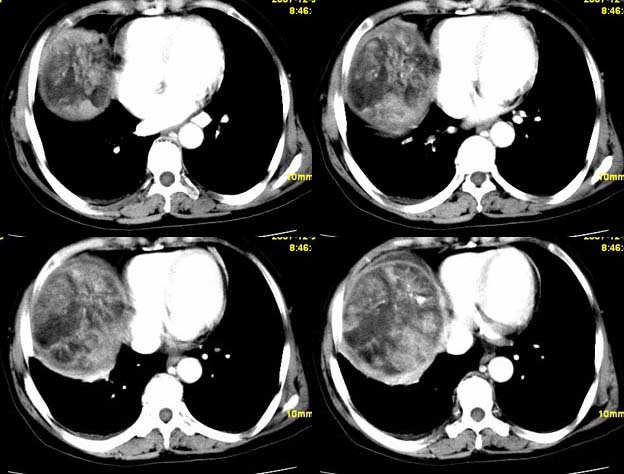

标题: CT11039:肝脏占位,平扫加增强,很“漂亮”的图像。

女,67,自诉右上腹痛10天,余病史未提供。

平扫低密度ct值约-14hu.